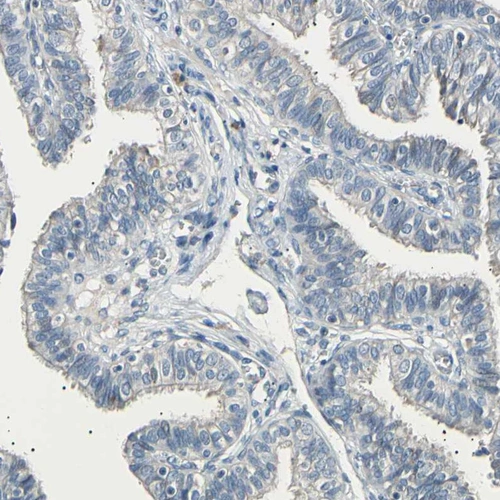

Immunohistochemical staining of human lung shows strong cytoplasmic positivity in macrophages.